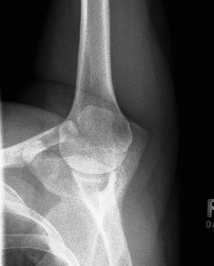

is this a normal or dislocated shoulder? in which direction is it dislocated?

dislocated, anterior